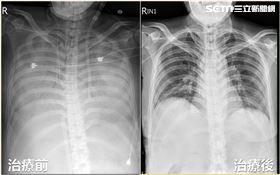

女肚痛住院照X光 醫驚:肺臟竟都消失了

台中32歲陳女因連日腹痛與下肢水腫在家跌倒就醫,檢查...